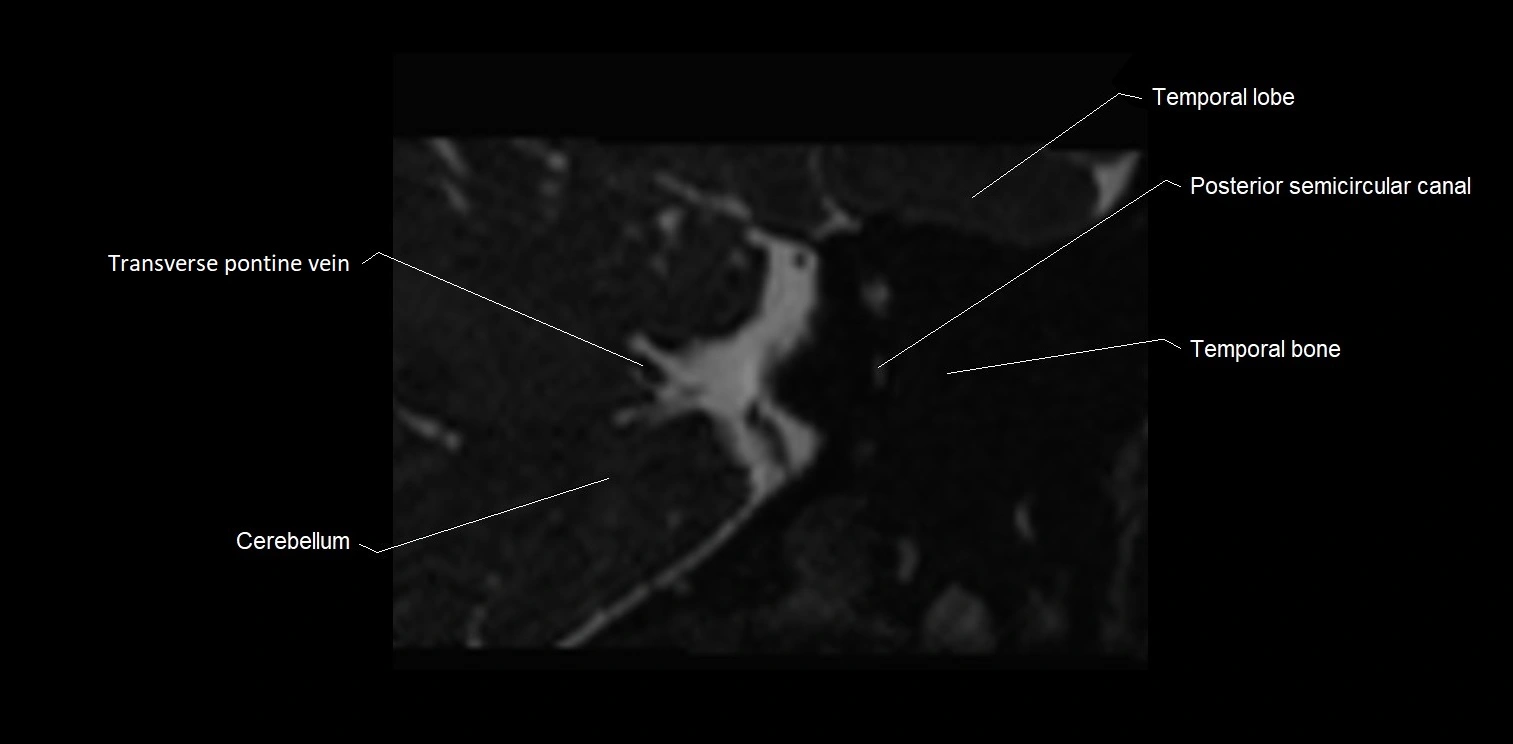

MRI images

image